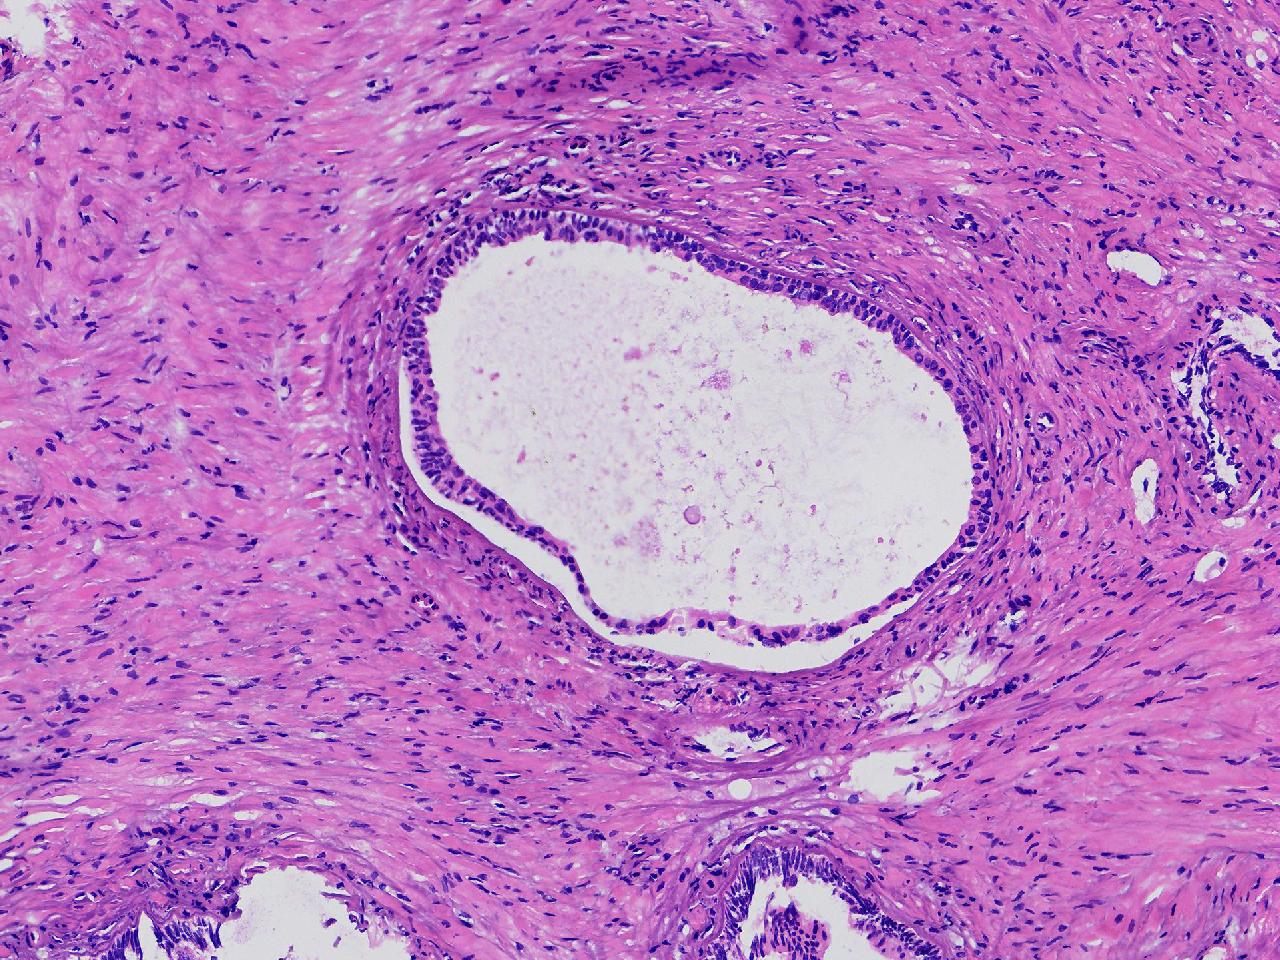

良性前列腺增生?

男,68岁,排尿困难半年余。行前列腺前切术。

前列腺电切标本

灰粉色条索状软组织多块,4X3X3厘米。

考虑为良性前列腺增生症

良性增生

BPH.